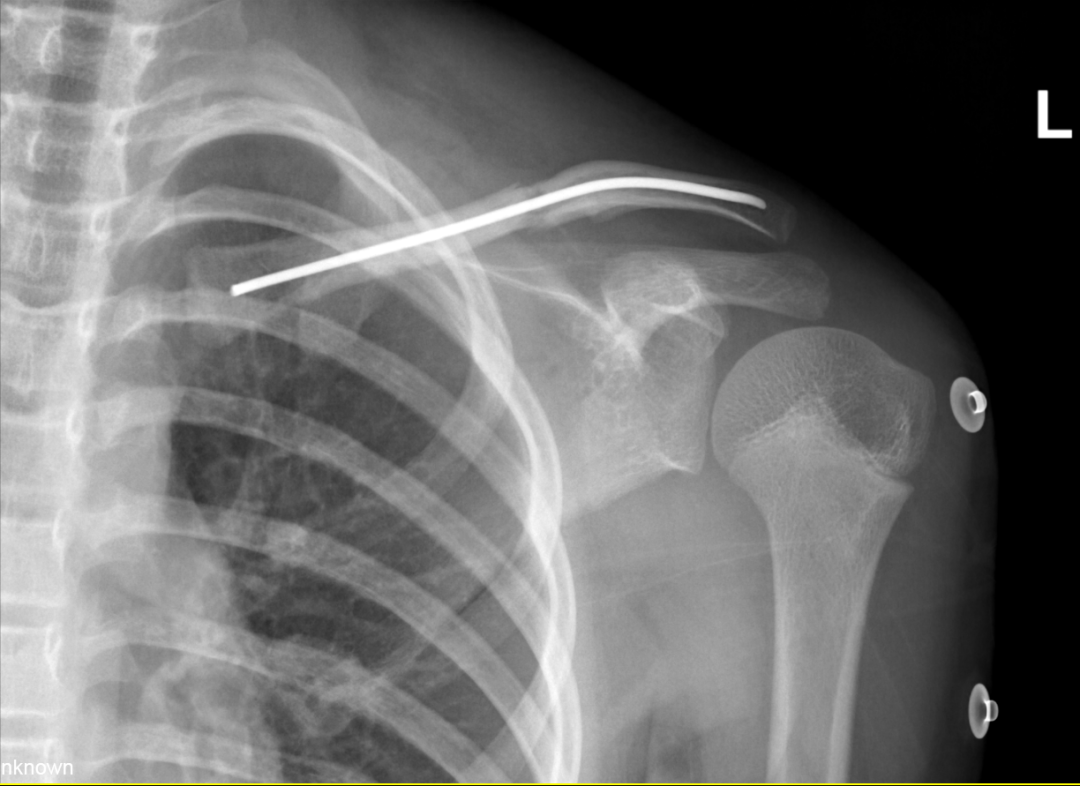

(术后X线片)

在详细了解手术过程后,小陈当天就办理了住院手续。手术仅用时30分钟,通过锁骨近端的小切口,顺利置入弹性髓内针,骨折达到解剖复位。

手术当天,整个过程仅用了25分钟,出血量不到5毫升。让小雨妈妈印象深刻的是:"手术结束后,孩子醒来第一句话就是'妈妈,我还能跳舞吗?'听到医生肯定的回答,我们都松了一口气。"